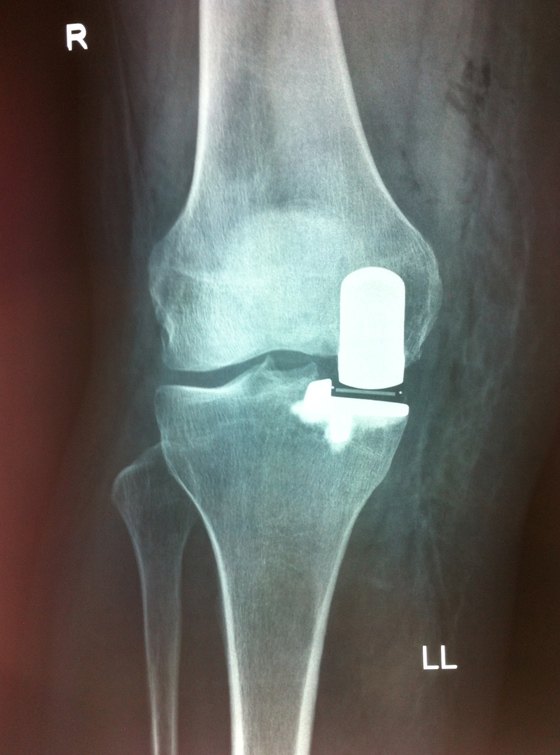

Partial knee replacement - medial unicompartmental knee replacement

Arthritis may affect only the inner half of the knee joint while the rest of the knee remains normal. In this situation, a medial partial knee replacement may be appropriate. In this operation, only the inner half of the knee is replaced. The normal parts of the knee are left intact.The surgeons at Melbourne Hip and Knee have extensive experience with the medial unicompartmental knee replacement including training for a year in Oxford with the developers of the world's most successful unicompartmental knee replacement, the Oxford Partial Knee Replacement.

The surgery is performed under an anaesthetic. An incision is made in the front of the knee and the knee joint is exposed. The ends of the femur and tibia on the inner half of the knee are cut and shaped. The replacement prostheses are then implanted. The wound is sutured closed.